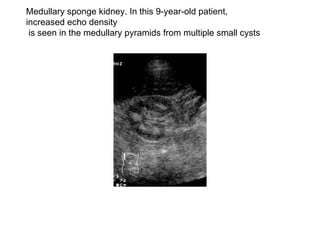

Medullary sponge kidney. In this 9-year-old patient, increased echo density is seen in the medullary pyramids from multiple small cysts